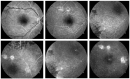

Eales disease manifests as an obliterative periphlebitis affecting the retina; it originates from the periphery and progresses posteriorly. It is characterized by retinal vessel wall inflammation, ischemia, and retinal neovascularization. In this report, we present the case of a 34-year-old male who attended our clinic with a sudden blurring of vision in his right eye. A diagnosis of bilateral retinal vasculitis with vitreal hemorrhage was ascertained in his RE. A dilated ocular fundus examination revealed perivenous sheathing of the peripheral vessels in both eyes. Fluorescein angiography indicated dye staining, vessel obliteration, capillary drop-out, areas of non-perfusion and the formation of new vessels. Laboratory tests revealed positive results for Borrelia; a PPD skin test and QuantiFERON TB assay were also positive. The patient underwent bilateral retinal laser pan-photocoagulation, followed by systemic treatment with oral steroids, cephazoline, isoniazid, azathioprine, and entecavir. The steroid dose was progressively reduced over 10 months; the treatment with azathioprine continues, as we are monitoring the patient over the long term. After 3 months, the vasculitis had regressed without any vitreal hemorrhage recurrence. Vision acuity improved from 0.4 to 1 in the patient's right eye. A multidisciplinary approach, which included collaborative management with gastroenterology, infectious disease, pulmonology, and rheumatology specialists, was essential for the diagnosis, treatment, and long-term follow up of the patient.